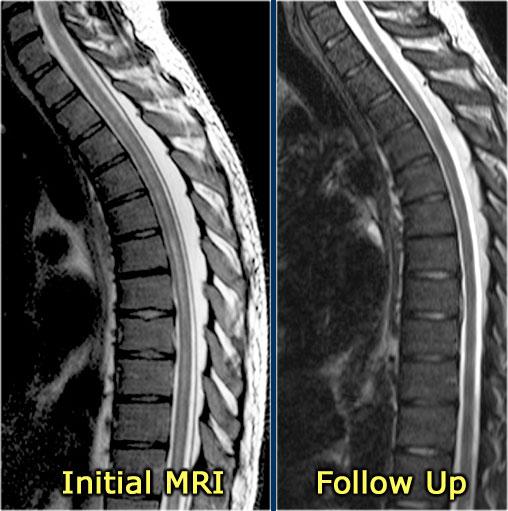

Hình ảnh MRI theo dõi cho thấy tủy sống đã trở về bình thường.

Bên trái là một trường hợp ADEM khác.

ADEM thường gặp ở trẻ em.

Một lần nữa có hình ảnh tổn thương lan tỏa tủy sống không ngấm thuốc và có tổn thương não kèm theo.

Tiếp tục xem hình ảnh theo dõi.

Hình ảnh theo dõi cho thấy gần như bình thường hóa hoàn toàn.